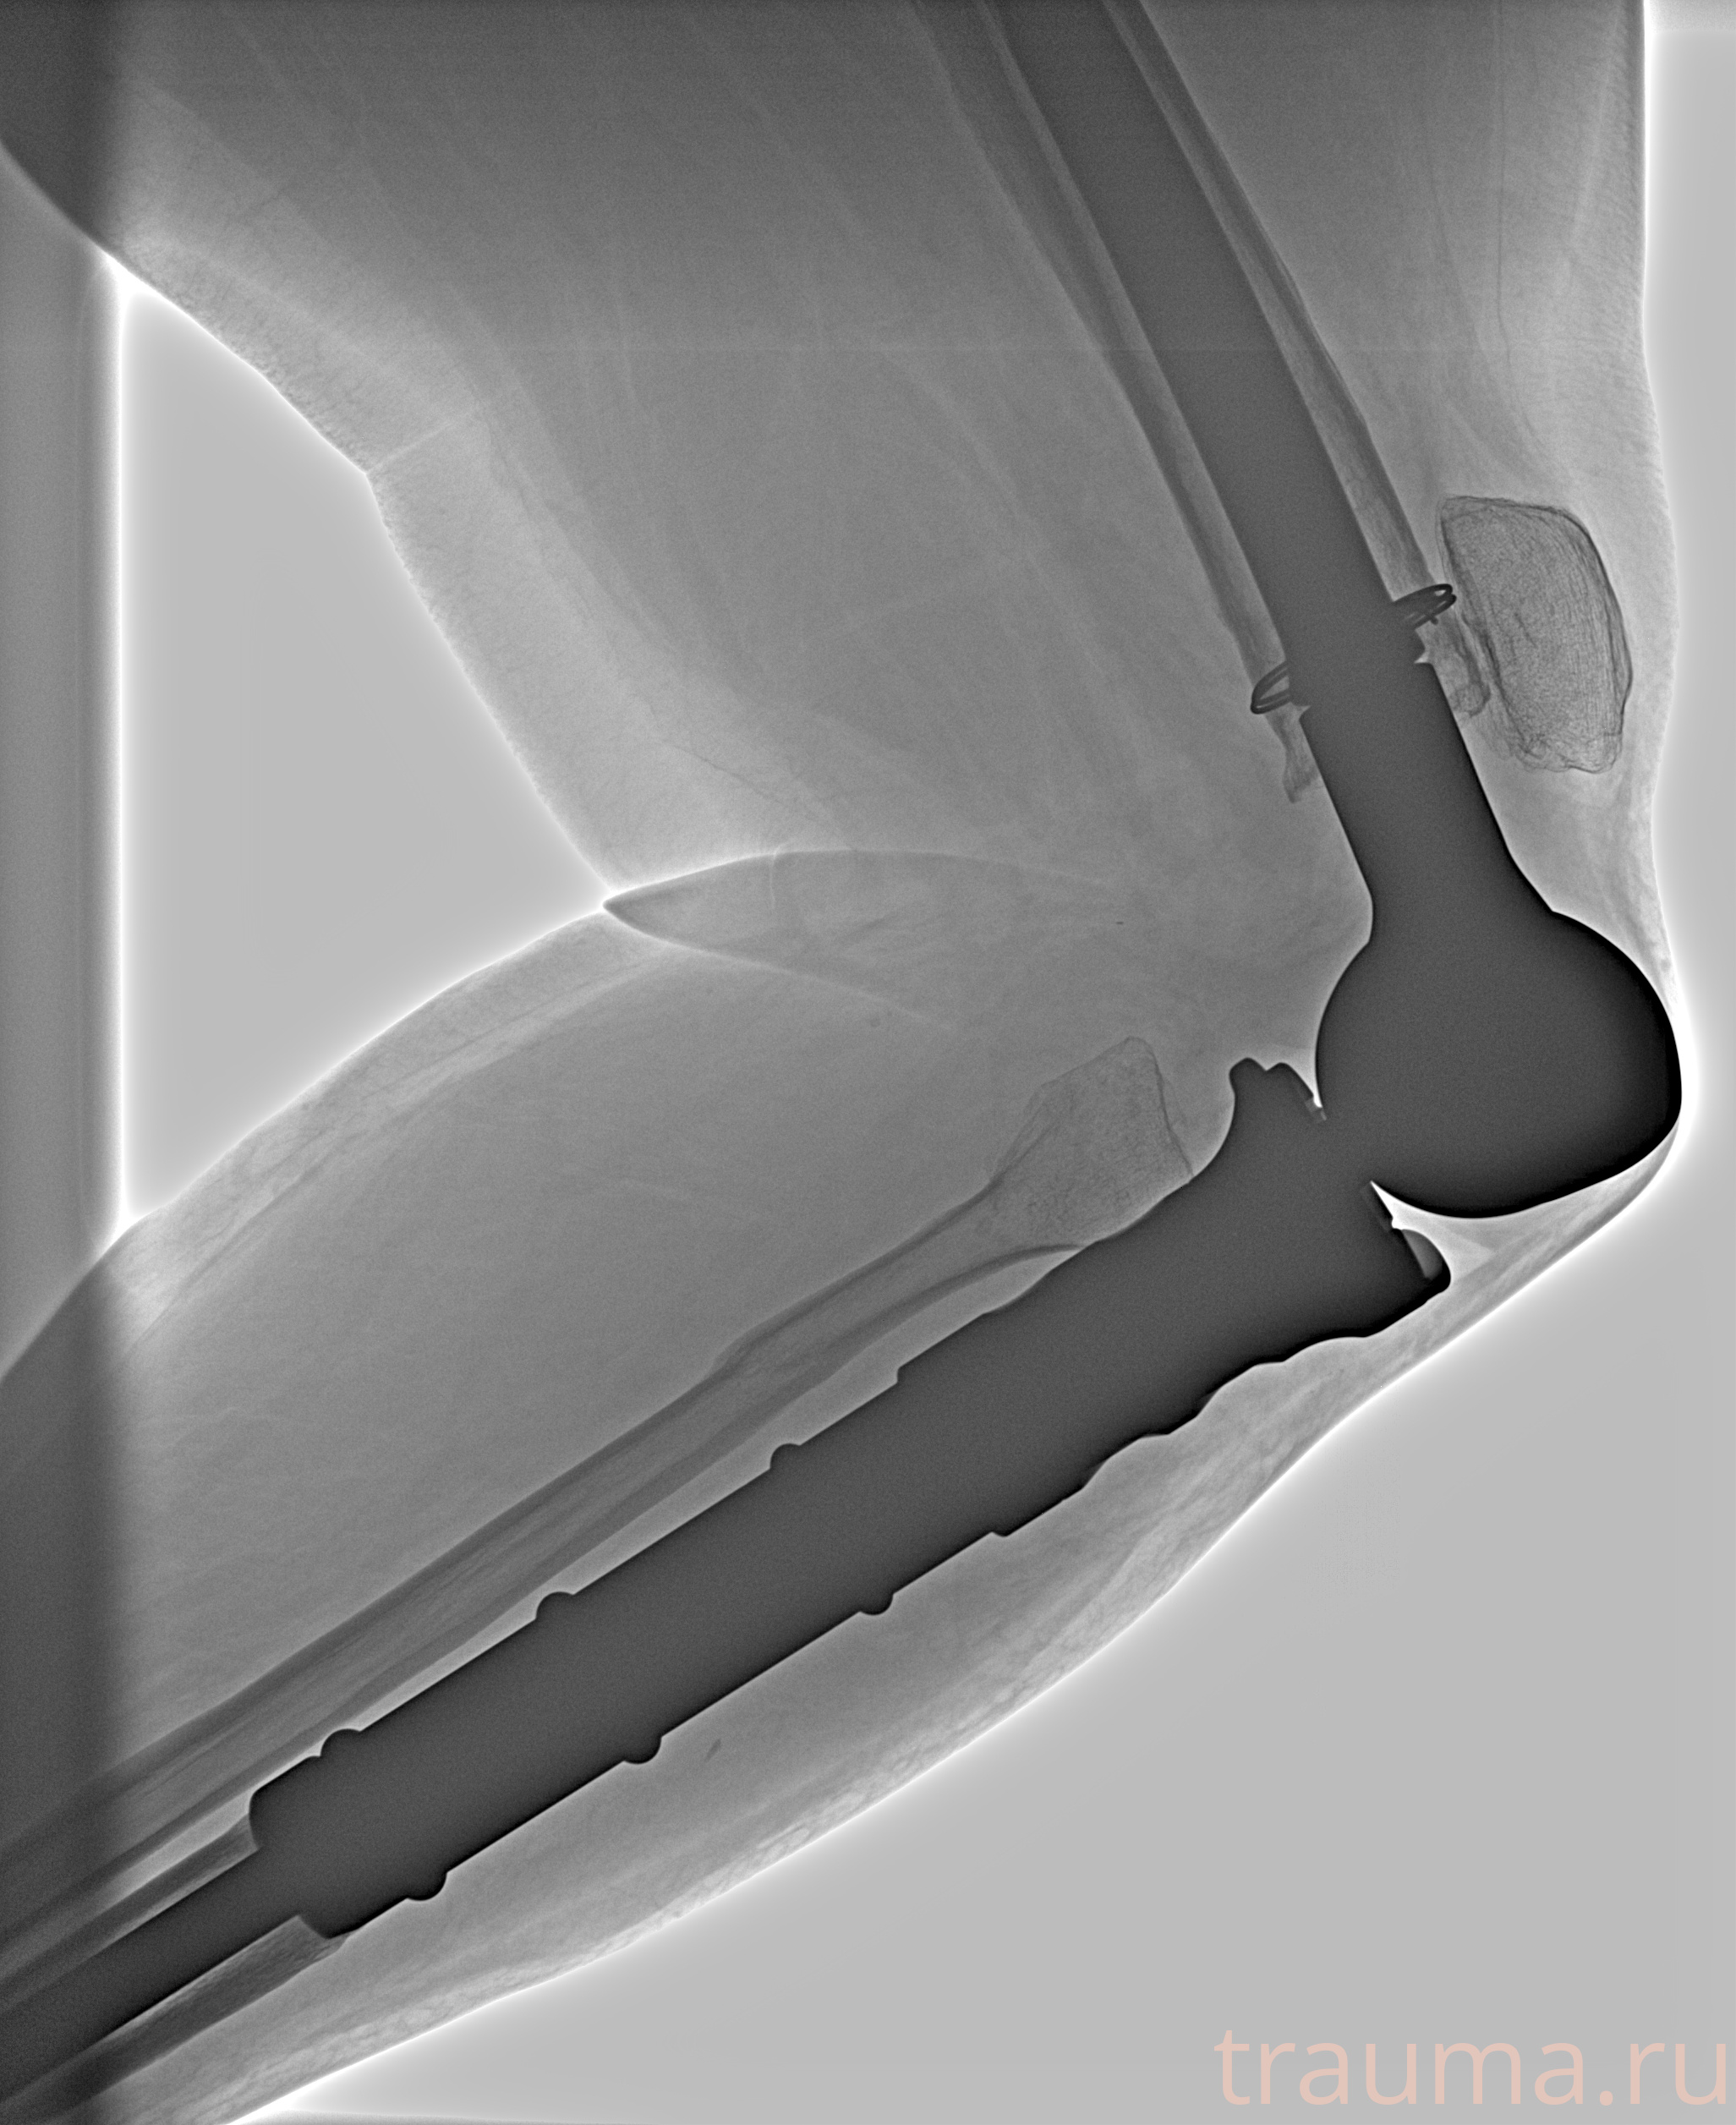

Рентгенограммы

Рентген на дому: по вашему адресу приезжает врач-рентгенолог, травматолог-ортопед с мобильным рентгеновским аппаратом, проводит диагностику травмы или заболевания, делает необходимые рентгенограммы, дает рекомендации по дальнейшему лечению. Получить качественные снимки в домашних условиях возможно благодаря уникальной методике, разработанной МосРентген Центром для института  Склифосовского